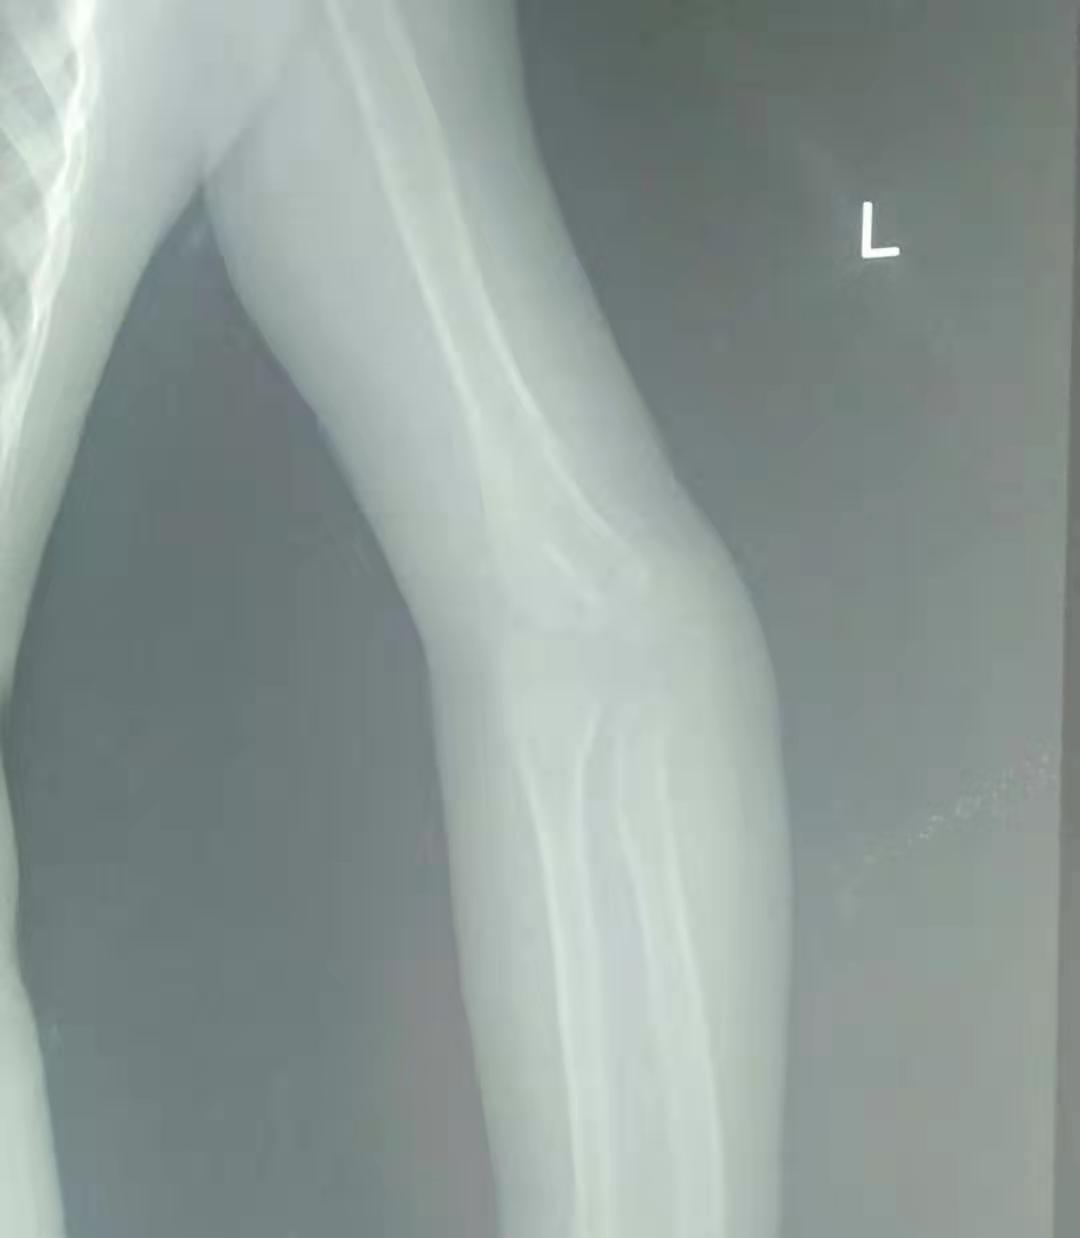

五岁的小女孩,因为小时候的意外导致了手肘骨折,当时不过一岁半的小女孩,没有及时告诉自己的妈妈,小女孩的妈妈发现了异常,小女孩手抬不起来,这可把这位妈妈给急坏了,立即带着孩子赶去了当地的医院,经过检查发现小女孩的手肘骨折错位,当时由于孩子太小,所以没有做手术,于是给予了手法复位,打了石膏,夹板;时隔两年,孩子的妈妈发现,孩子手肘与正常的手肘有些不一样,因为孩子太小,医生提议在孩子在大点的时候给予手术修型纠正。孩子的手有些畸形,没有出现什么功能障碍,只是对于一个孩子来说,影响外形。

骨折的手

对于儿童而言,骨折的愈合速度是成人的1/2,在幼儿期会更快,所以如果在骨折后没有很好的复位的话,对于年幼孩子来说,愈合后可能会导致肢体畸形或者功能障碍。有时候不同部位的骨折复位良好,也会出现因为本身愈合能力差的原因,导致不愈合性可能。

骨折不复位,容易破坏血液循环,形成骨不连,患者破坏小儿的骨骺,形成肢体生长畸形。